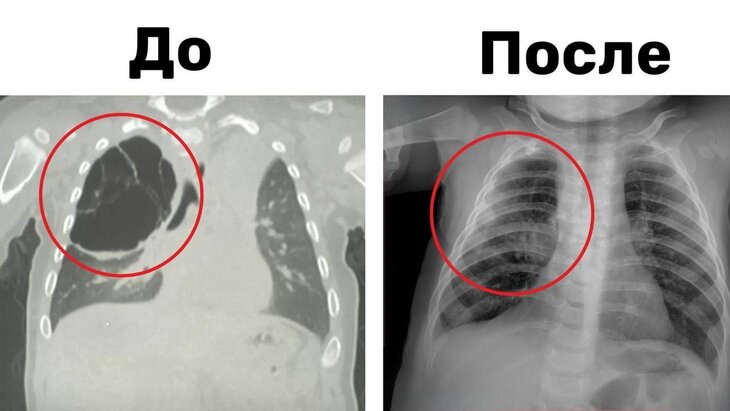

В Подмосковье ребенку удалили 15-сантиметровую кисту легкого